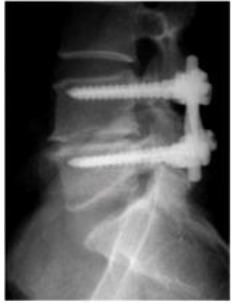

Sobre a imagem abaixo assinale a alternativa correta: